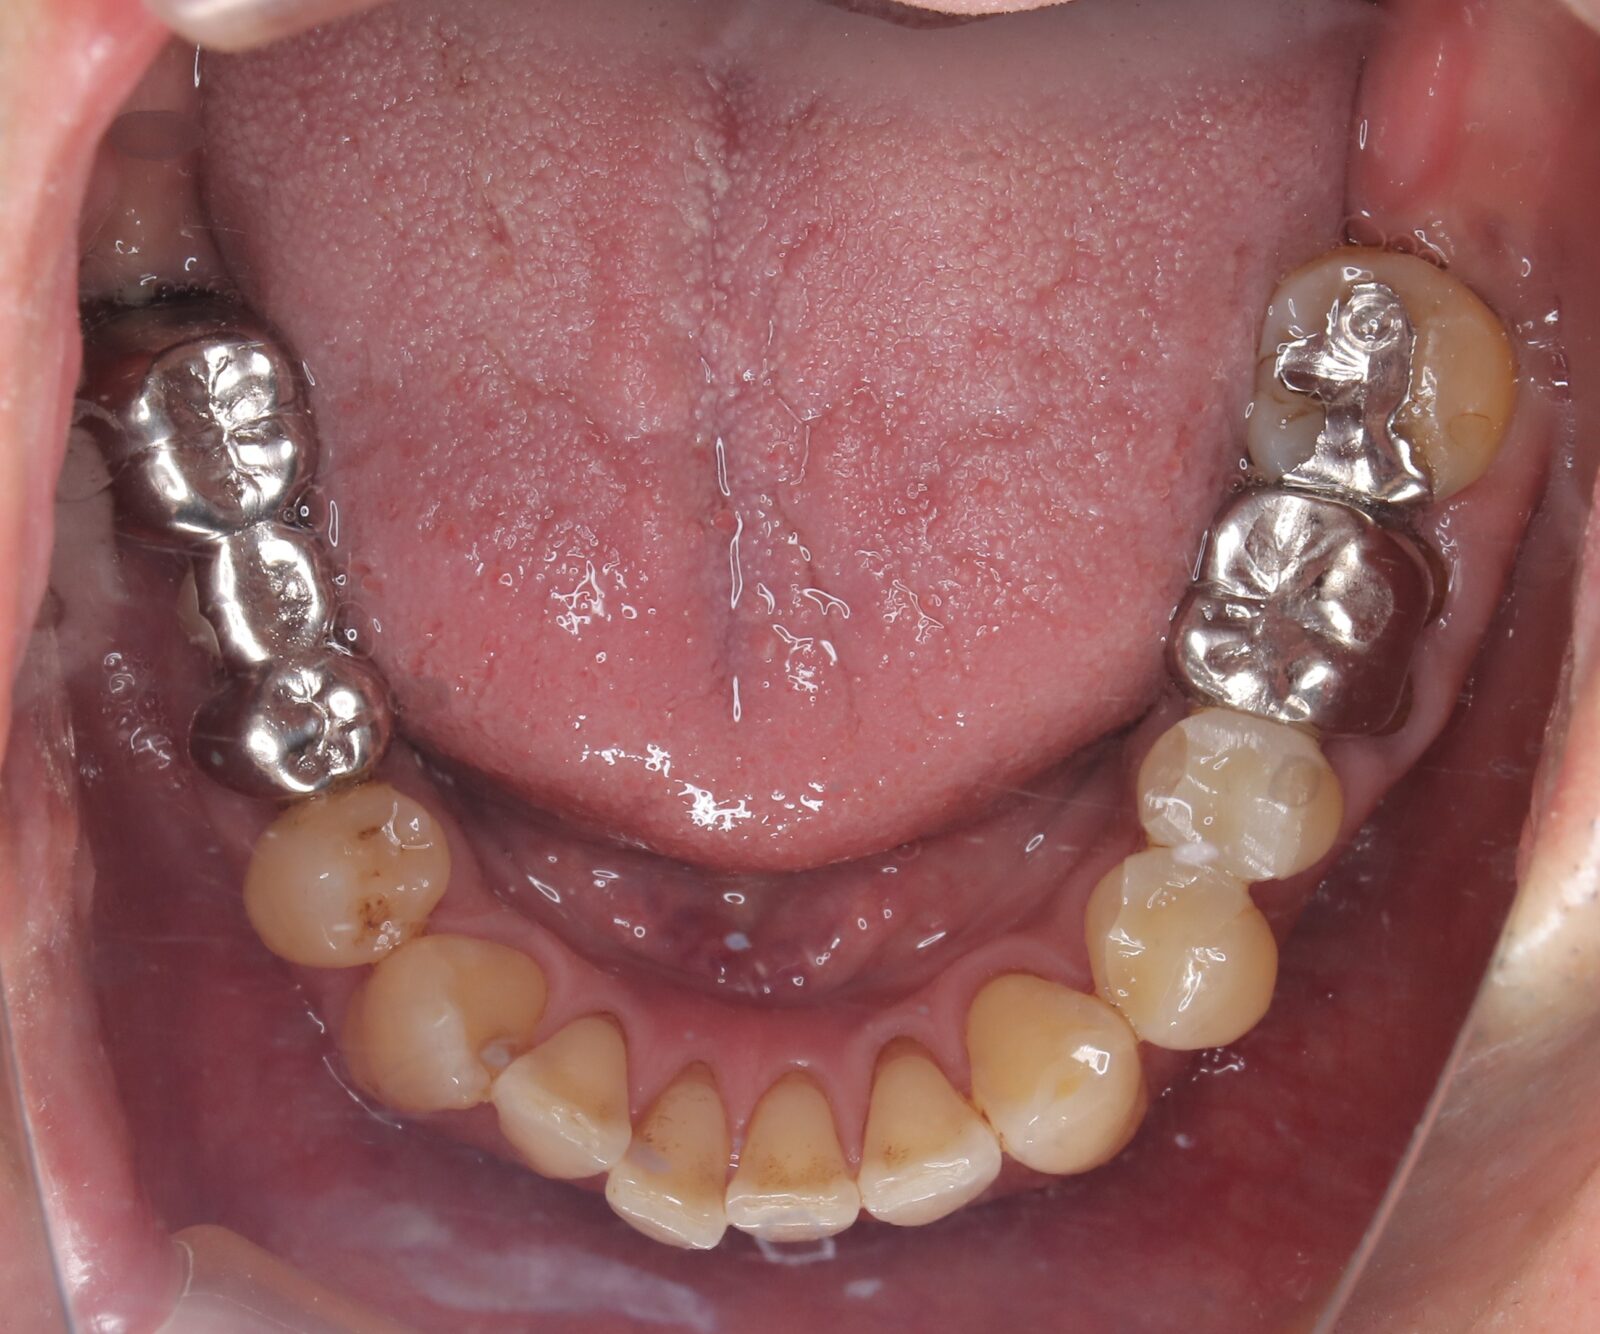

矯正と補綴が必要で実施した症例

左側に隙間。歯の数が少ない。もともと2番と7番がない。(先天欠如)歯の数が少ないため上顎のアーチ全体が小さい。歯槽骨の幅も狭く、歯肉も薄い。骨質も弱かった。

上顎左右2番と6番が先天欠如。下顎左右1番も先天欠如でもともとブリッジが装着されていた。

左右非対称なすきっ歯。上顎の前歯がないので左側の隙間を左右2番相当部に集めた。

上下の前歯が反対の噛み合わせ(受け口)で、干渉しているためうまく閉じることができず、奥歯は左右同時に噛めないので、どこかにずらさないと口を閉じられない。

左右の歯を同時に合わせることができず、どこで噛んだら良いかわからない噛み合わせでした。

小臼歯部は噛み合うことがない側方の開口状態。矯正と補綴が必要なケース。 主訴は顎の不調と歯軋り、夜間の食いしばり。

マルチブラケットとインビザラインを併用し、クラウンとブリッジを装着しました。

上顎左右2番は、歯が入るスペースを作り、ブリッジを装着しました。

他の歯医者で何軒も断られていました。 骨の幅がうすくインプラントはできない。骨の質も柔らかい。PCR検査の結果も歯周病ハイリスク患者でした。

歯の位置は、本人の顎が安定する場所を探して着地した。 左右で噛み合わせが非対称で、理想的な歯のポジションを獲得できなかったものの、左右同時に噛むことができるようになった。

顎関節の症状も落ち着いて、開口障害や、顎の痛みは無くなった。

矯正治療はどの装置を選択しても歯周病のリスクを高めてしまう。

これ以上の歯の移動が歯周病と骨質、骨の代謝のバランスの兼ね合いで困難であると判断し、ここが着地点とした。